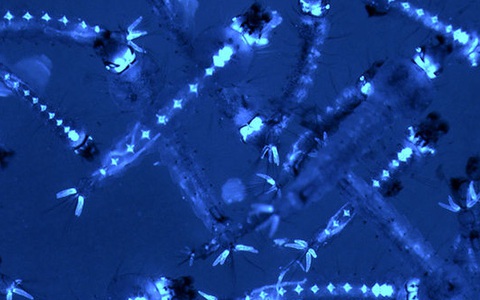

Ký sinh trùng sốt rét

TTO - Ngày 4-6, TS.BS Hồ Đặng Trung Nghĩa, trưởng khoa nhiễm Việt - Anh (Bệnh viện Bệnh nhiệt đới TP.HCM), cho biết bệnh viện đang điều trị hai bệnh nhân nhập cảnh từ châu Phi bị sốt rét ác tính với mật độ ký sinh trùng sốt rét cao.

Các nhà khoa học quốc tế đã thử nghiệm cách tiếp cận mới, tiêu diệt các ký sinh trùng sốt rét ngay từ giai đoạn ủ bệnh.